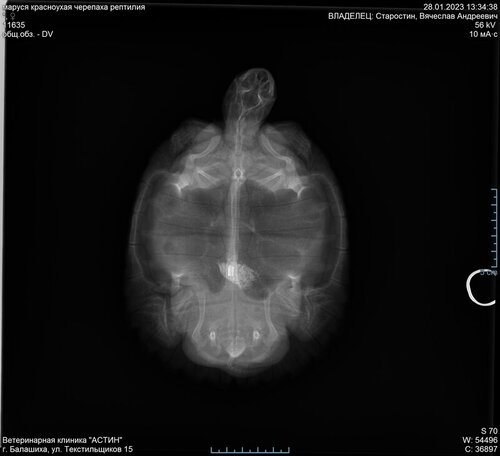

сделали рентген и оказалось что черепашка что-то скушала и это что-то находится у неё в животе. Из-за этого у неё болел живот и было такое странное поведение. Сделали необходимые процедуры, влили вазелин, теперь осталось наблюдать.

E35D4A48-7E3F-4F41-9569-5BF06E330561.jpeg

FF39C4DE-BCCF-4572-99C1-7191A9BF3519.jpeg

1C85DD83-3E54-4588-9C90-9954143AEBEC.jpeg